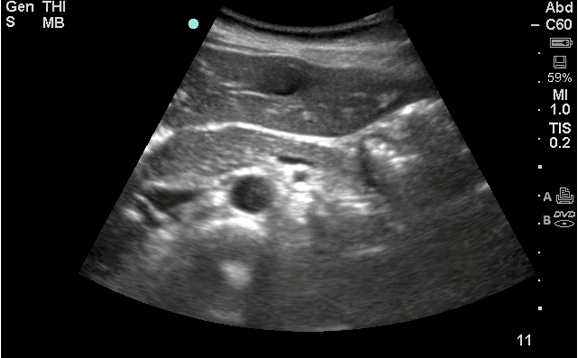

The initial diagnostic test ordered was a chest radiograph, which showed 80% opacification of the right hemithorax, consistent with pneumonia and associated parapneumonic effusion seen in Figure 1. A bedside ultrasound was subsequently performed in the ED, initially in order to examine the size of the pleural effusion in which a startling discovery was made…..”